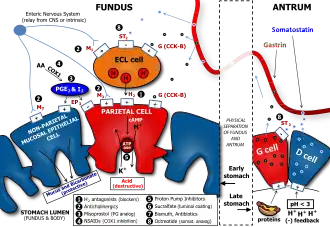

There are two types of gastric gland, the exocrine fundic or oxyntic gland, and the endocrine pyloric gland. The major type of gastric gland is the fundic gland that is present in the fundus and the body of the stomach making up about 80 per cent of the stomach area. These glands are often referred to simply as the gastric glands. The fundic gland contains the parietal cells that produce hydrochloric acid and intrinsic factor, and chief cells that produce pepsinogen and gastric lipase.

The pyloric gland is found in the pyloric region, the remaining 20 per cent of the stomach. The pyloric glands are mainly in the pyloric antrum. The pyloric gland secretes gastrin from its G cells. Pyloric glands are similar in structure to the fundic glands but have hardly any parietal cells.

- Parietal cells ("parietal" means "relating to a wall"), also known as oxyntic cells are most numerous on the side walls of the gastric glands. The parietal cells secrete hydrochloric acid (gastric acid). This needs to be readily available for the stomach in a plentiful supply, and so from their positions in the walls, their secretory networks of fine channels called canaliculi can project and ingress into all the regions of the gastric-pit lumen. Another important secretion of the parietal cells is intrinsic factor. Intrinsic factor is a glycoprotein essential for the absorption of vitamin B12.[1] The parietal cells also produce and release bicarbonate ions in response to histamine release from the nearby ECLs, and so serve a crucial role in the pH buffering system.[11]

- Enteroendocrine cells – They are usually present in the basal parts of the gastric glands, which is differentiated into three cell types – enterochromaffin like cells (ECL cells), G cells, and D cells.

- Enterochromaffin-like cells (ECL cells) – They release serotonin and histamine. These cells store and release histamine when the pH of the stomach becomes too high. The release of histamine is stimulated by the secretion of gastrin from the G cells.[1] Histamine promotes the production and release of HCL from the parietal cells to the blood and protons to the stomach lumen. When the stomach pH decreases (becomes more acidic), the ECLs stop releasing histamine.

- G cells – They secrete gastrin hormone. Gastrin stimulates the gastric glands to release gastric acid. These cells are mostly found in pyloric glands in the pyloric antrum; some are found in the duodenum and other tissues. The gastric pits of these glands are much deeper than the others and here the gastrin is secreted into the bloodstream not the lumen.[12]

- D cells – D cells secrete somatostatin. Somatostatin suppresses the release of hormones from the digestive tract.

Layers of stomach wall Gastric acid regulation